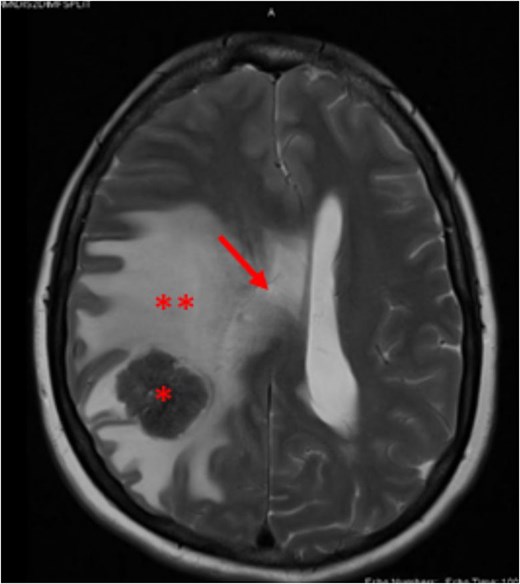

At baseline, her vital signs were within normal range, physical examination was unremarkable, and there were no focal neurologic deficits. Laboratory tests, including the complete metabolic panel, were within normal range except for the low hemoglobin (10.2 g/dl). Due to the severity and chronicity of her symptoms, a brain computed tomography (CT) scan was performed which showed a lesion of the right parietal lobe, surrounding edema, and central hyperdense area, with midline shift and effacement of the ipsilateral right lateral ventricle. Magnetic resonance imaging (MRI) of the brain showed an intra-axial lesion, measuring of 2.6 × 2.3 × 2.6 cm, in the right parietal lobe with small frontal extent. Additionally, it was surrounded by significant vasogenic edema, showed mass effect evidenced by effacement of adjacent sulci, compression of right lateral ventricle, 6 mm leftward shift of midline structures, and mild herniation of right cranial vault (Fig. 1). The working diagnosis was a brain tumor with mass effect, so the patient underwent right parietal craniotomy and resection of the intra-axial solid tumor. Intraoperative frozen section showed adenocarcinoma with clear resection margins. The postoperative course was uneventful, and she was discharged home after 7 days. Surprisingly, final histopathological report showed metastatic adenocarcinoma with morphological and immunohistochemical features favoring a colorectal origin.

Brain MRI T2 weighted image, showing right parietal lobe lesion (asterisk), surrounded by edema (**) and causing right lateral ventricular compression with midline shift (arrow).